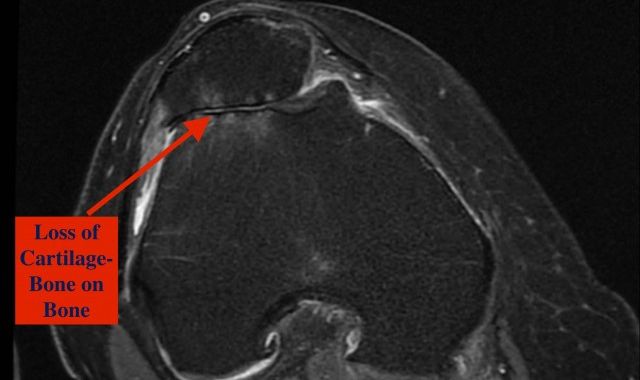

What is Osteoarthritis?

Attached video explains simply what osteoarthritis is and how it manifests as a painful... -